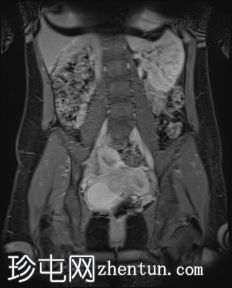

盆腔增强 MRI 检查增强了我们对 CT 扫描中发现的病变的理解。右肾发育不全,左肾肥大伴肾积水,双子宫完整,阴道隔膜,发育不全侧阴道积血。

双侧卵巢均有多个功能性囊肿,右侧卵巢可见黄体囊肿。

CT和MRI检查结果为Herlyn-Werner-Wunderlich综合征的典型表现,其特征为经典的三联征:III型苗勒氏管异常(完全性双子宫)、中肾管异常(肾发育不全)以及肾发育不全侧阴道积血。

该患者左肾积水是偶然发现的,且无任何明确的梗阻原因,例如泌尿系统结石、

肿瘤